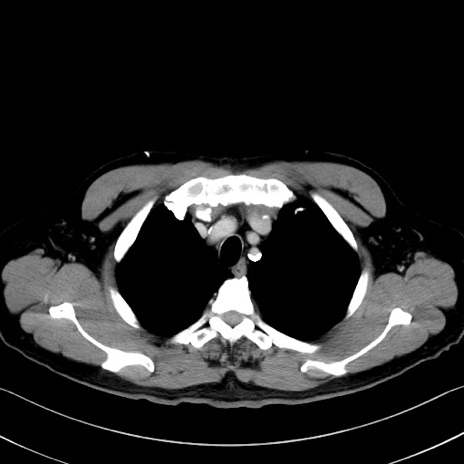

症例35(横断像)

【症例】70歳代 男性

【主訴】腹部膨満、嘔吐

【現病歴】昨日より腹部膨満感出現。本日増悪し、仙痛出現。嘔吐あり、受診。

【既往歴】糖尿病、胆摘後

【身体所見】BP 149/80mmHg、HR 74/min、BT 35.9℃、腹部:膨満、軟、圧痛なし。腸雑音減弱あり。上腹部正中切開瘢痕あり。

【データ】WBC 13500、CRP 1.72